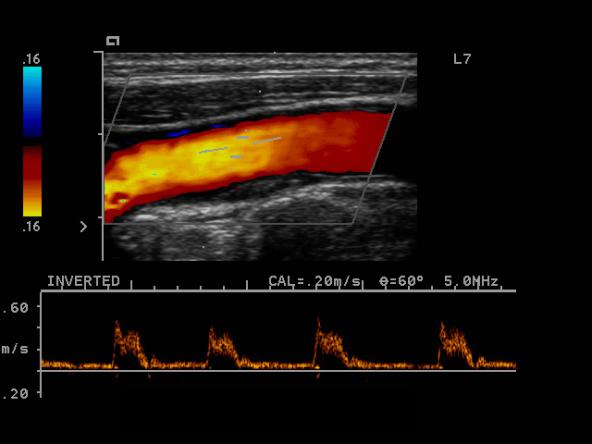

三、颈动脉彩超与经颅多普勒超声(TCD)

颈动脉超声是诊断、评估颈动脉壁病变的有效手段之一,可清晰显示血管内中膜是否增厚、有无斑块形成,斑块形成的部位、大小、斑块性质以及是否有血管狭窄、狭窄程度、有无闭塞等,还可对检测血管的血流动力学结果进行分析。优点是简便、无创、价格不高,各级医院均可开展,缺点是只能评价局部血管、受设备和操作人员技术水平限制检测结果可能存在差异性。